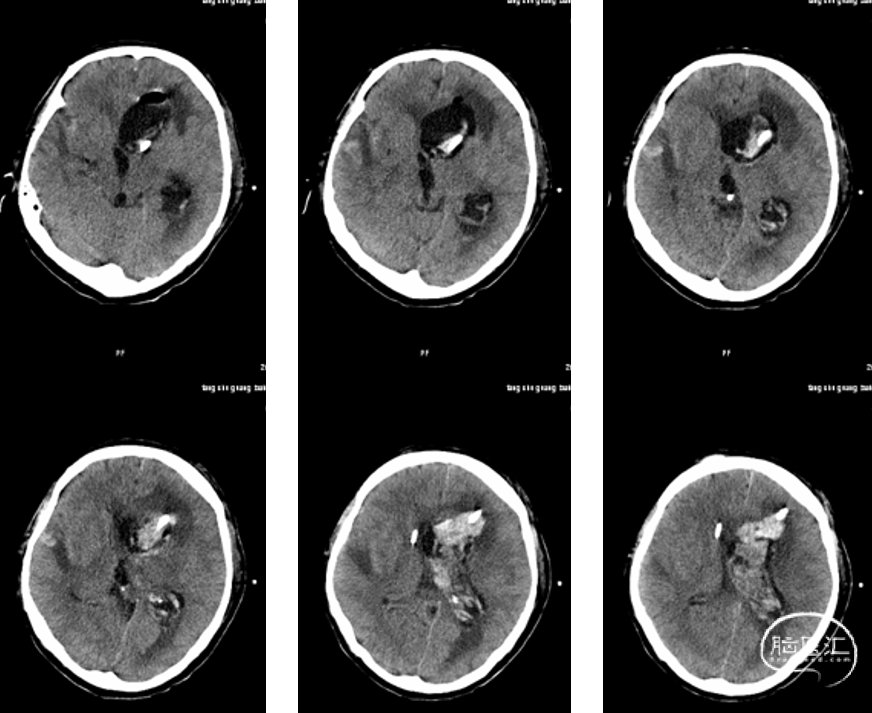

当天急诊行内镜下脑室冲洗术及左侧脑室外引流术,术中见脑脊液混浊,脑室内充满絮状物,脑室内结构无法辨认,无法造瘘。钳取脑室内絮状物送检。